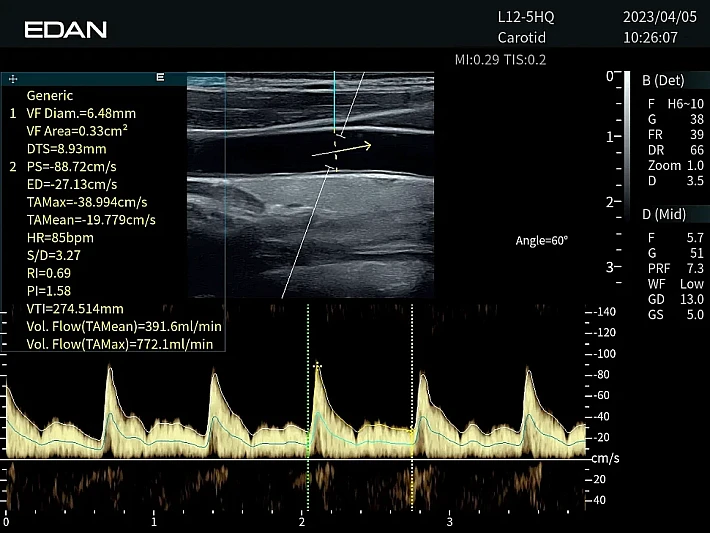

Медицинское оборудование и сервисное обслуживание